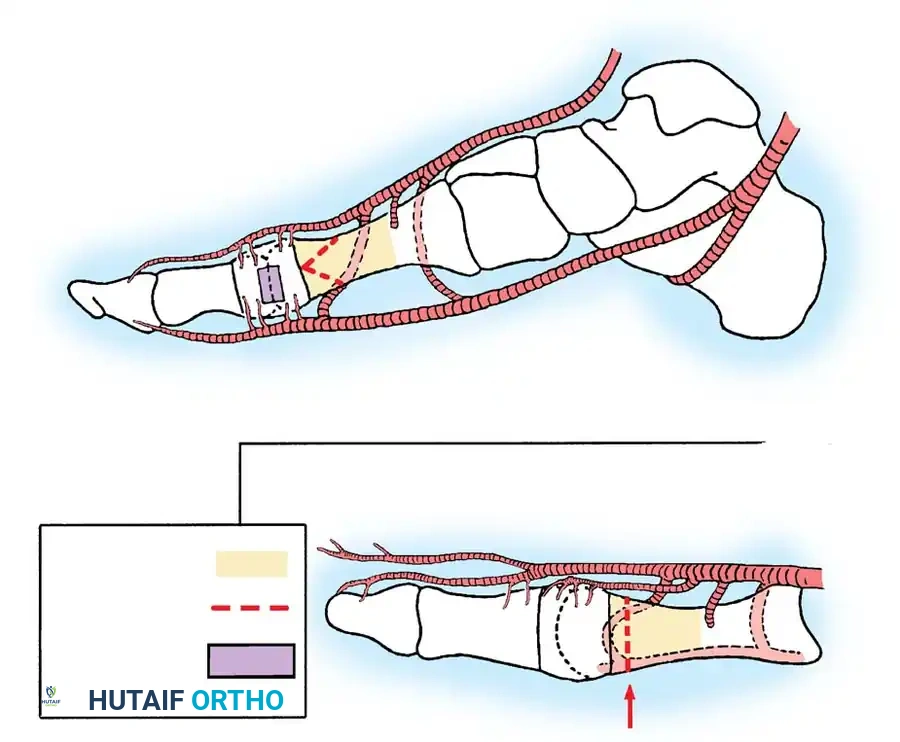

REMOVAL OF THE FIBULAR SESAMOID

• When the medial eminence and phalangeal base have been excised, remove the fi bular sesamoid.

• Place a sturdy two-toothed retractor beneath the metatarsal head, and have an assistant lift it dorsally.

• Using a Freer elevator or a small osteotome for its strength, mobilize the fi bular sesamoid (Fig. 78-31A to C). This may be diffi cult in elderly patients with signifi cant deformity and adherence of the sesamoid to the metatarsal head. Lift the metatarsal dorsally for exposure (Fig. 78-31D and E).

• When the sesamoid is mobile, identify the fl exor hallucis longus tendon by placing traction on the hallux and fl exing and extending the interphalangeal joint of the hallux. The tendon is visible just distal to and in alignment with the sesamoids, which straddle it.

• Identify and expose the lateral neurovascular bundle just lateral to the tendon by blunt dissection.

• Pull the plantar medial capsule medially. This requires a fi rm grasp on the capsule. The medial traction brings the intersesamoid “ligament” into better view.

• Incise the intersesamoid ligament longitudinally with a No. 67 Beaver or No. 15 Bard-Parker blade. If tenotomy scissors are used, place one arm of the scissors under the ligament (this arm rests on the dorsal side of the fl exor hallucis longus) and the other arm dorsal to the ligament.

• When the intersesamoid ligament is incised, grasp the sesamoid fi rmly with forceps or a small Kocher clamp, fl ex the toe at the interphalangeal and metatarsophalangeal joints to relax the fl exor hallucis longus tendon, and pull the fi bular sesamoid distally and medially.

• With release of the intersesamoid ligament, the medial surface of the fi bular sesamoid is free from soft tissue. Distally, the sesamoid is free because of resection of the base of the proximal phalanx. This leaves two sides of the sesamoid, distal and medial, free of soft tissue.

• While pulling the sesamoid distally and medially, use a small blade to incise along the lateral margin of the sesamoid under direct vision. Keep pulling the head of the metatarsal dorsally and holding the hallux distracted and in fl exion. This greatly aids in identifi cation of the margins of the fi bular sesamoid, particularly laterally and proximally.

• The most diffi cult part of the sesamoidectomy and that which should be done last is release of the proximal lateral corner of the sesamoid where the fl exor hallucis brevis lateral head inserts. While incising the lateral capsular attachments to the sesamoid, do not bury the blade of the knife because the neurovascular bundle to the lateral side of the hallux is just lateral to the capsule.

• Now all attachments to the fi bular sesamoid have been removed except the lateral head of the fl exor hallucis brevis, which inserts on the proximal lateral margin of the sesamoid. This is a diffi cult section to remove; however, this section can be released under direct vision by pulling the sesamoid distally and medially and lifting the metatarsal head dorsally with a strong two-toothed retractor.

• When the sesamoid has been removed, insert two 0.062-inch Kirschner wires retrograde from the tip of the toe 2 to 3 mm plantar to the nail bed, leaving about 5 to 7 mm of the pins exposed at the base of the phalangeal remnant to help align the phalanx on the metatarsal before antegrade passage of the pins into the metatarsal (Fig. 78-31F).

LATERAL DISPLACEMENT OF THE FIRST METATARSAL

• Push the metatarsal laterally several times. Occasionally, this does not move the metatarsal, but some lateral mobility usually is present.

Fig. 78-31 Excision of fi bular sesamoid in modifi ed Keller procedure. With base of proximal phalanx removed and medial eminence excision, exposure of fi bular sesamoid is not as diffi cult from medial incision. A, Operative photograph showing elevation of fi rst metatarsal with strong two-tooth retractor and use of small osteotome to mobilize fi bular sesamoid and lateral capsuloligamentous (frequently contracted) structures. Osteotome is between metatarsal head and lateral sesamoid. When mobilization of fi bular sesamoid is complete, entire sesamoid is visible for excision. Note chondromalacia of tibial sesamoid articular surface medial to osteotome. B, Fibular sesamoid has been excised, and lateral capsular structures and conjoined tendon (in forceps) have been released. Neurovascular bundle to lateral side of hallux is adjacent to these structures. C, Diagrammatic representation of modifi ed Keller procedure. By excising fi bular sesamoid, valgus moment of conjoined tendon of fl exor hallucis brevis and adductor hallucis no longer pulls fl exor hallucis longus tendon laterally (carrying hallux with it) through capsulosesamoid plantar plate and pulley system. D, Metatarsal head must be lifted dorsally to excise fi bular sesamoid under direct vision. E, Note exposure of fi bular sesamoid after mobilization of metatarsal head. Continued

Fig. 78-32 Firm fi brous band connects fi bular sesamoid to base of proximal phalanx. Traction on band pulled hallux into valgus. Removing fi bular sesamoid and holding hallux straight for 4 weeks improved results.

Presumably, the laterally displaced fi bular sesamoid, when pulled proximally by the lateral head of the relaxed fl exor hallucis brevis, pulls the fl exor hallucis longus laterally through the sesamoid apparatus, which encases it and contributes to recurrent hallux valgus. In addition, while reoperating after a failed Keller procedure, we observed a strong, linear, fi brous attachment of the fi bular sesamoid to the proximal phalangeal remnant (Fig. 78-32), which pulled the hallux into valgus when tension was applied to it. For these reasons, when the deformity is severe, the hallux and fi rst metatarsal maintain better alignment if excision of the fi bular sesamoid and lateral displacement of the metatarsal are added to the procedure. joint, lateral capsulotomy at the metatarsophalangeal joint, and lengthening of the extensor hallucis longus tendon. Hohmann recommended lateral displacement and plantar tilting of the distal fragment, following osteotomy at the metatarsal neck to correct hallux valgus. In 1945, a report by Mitchell et al. of 100 osteotomies gave the procedure his name. Since then, several authors have presented large retrospective reviews of the Mitchell operation to correct hallux valgus in adults and adolescents, with satisfactory results ranging from 74% to 94%. Gibson and Piggott described a peg-in-hole distal metatarsal osteotomy that differed from the Mitchell procedure in its use of a lateral plantar spike on the proximal fragment in place of the lateral spike on the distal fragment (as recommended by Mitchell). The nonunion rate has been negligible in all series of the Mitchell procedure, and recurrence of the deformity has been infrequent. The most troublesome complication has been metatarsalgia, attributable to dorsifl exion malunion of the distal fragment, excessive shortening of the metatarsal, or both (Fig. 78-33). In a long-term (average 21 years) follow-up study of 105 Mitchell procedures, Fokter, Podobnik, and Vengust found that the most common complication was recurrent hallux valgus with medial eminence pain. Their good-to-excellent results deteriorated from 97% at follow-up ranging from 2 to 11 years to 64% at follow-up ranging from 15 to 24 years, primarily because of recurrence of deformity with medial eminence pain. The use of a Kirschner wire for fi xation (instead of sutures) prevented malunion; all osteotomies healed in 6 weeks with only secondary displacement. Likewise, with the pegin-hole procedure, metatarsalgia has been the most common complication. Relief of pain, narrowing of the forefoot, and correction of the deformity have been achieved in most patients, however. A closing wedge osteotomy at the subcapital level of the fi rst metatarsal to correct valgus of the hallux also has its proponents. Although opponents emphasize that metatarsus primus varus is worsened, and recurrence of the valgus deformity of the great toe is likely, published series have not confi rmed this. Of 32 osteotomies reported by Peabody and 76 reported by Funk and Wells, no nonunions or signifi cant recurrences of the deformity were recorded. A popular osteotomy of the distal metatarsal is the chevron intracapsular osteotomy, which was described by Corless in 1976 as a modifi cation of the Mitchell procedure to correct the bunion associated with mild-to-moderate metatarsus primus varus. The procedure consists of two parts: (1) correction of metatarsus primus varus by a V shaped osteotomy in the sagittal plane through the metatarsal head and neck, followed by lateral shifting of the metatarsal head and trimming of the proximal fragment without internal fi xation (because of the inherent stability of the osteotomy) and (2) correction of the hallux valgus by suturing a previously raised fl ap of joint capsule into the abductor hallucis tendon. Several series of this osteotomy with adequate clinical follow-up have been published. Austin and Leventen reported, in 100 osteotomies randomly selected for analysis from a group of 1200, that no nonunions, osteonecrosis, or infections occurred. Hattrup and Johnson reported, in 225 feet (157 patients), that pain, shoe fi t, and cosmesis were improved in all but a few patients. Because their best results were in younger patients, the authors indicated that